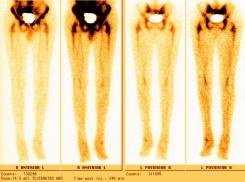

Nuclear Scan Images of Lower Torso & Lower Legs

These images were captured in order to determine why Liam’s bones broke so easily playing a video game and to also determine if there

was any Osteomyelitis. This is the diagnosis report from the scan. "There is mild increased activity noted in the lateral side of the left

ankle. However the patient does have a cast on the left leg. This uptake can be secondary to either inflammatory or infectious change within

either the skin or adjacent bone." Various contrast were used to enhance image details. The last images reminds one of the Shroud of Turin.

Hummm, makes one wonder... ;-)